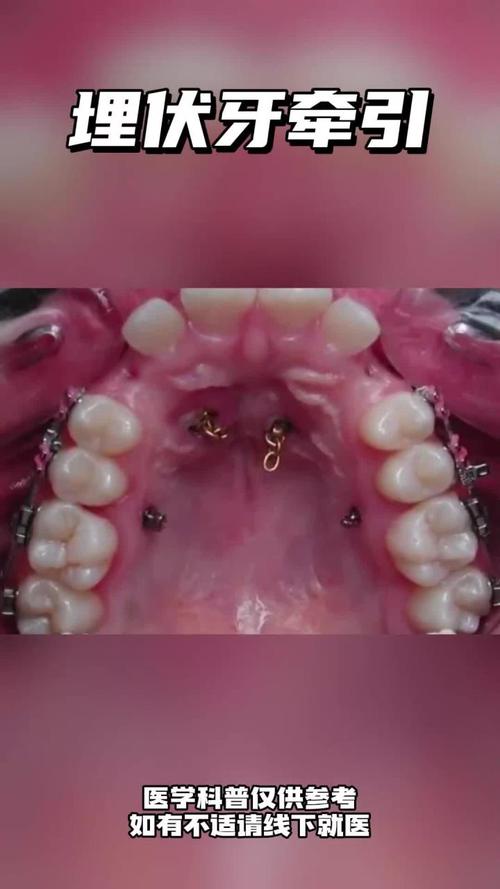

牙齿牵引是正畸治疗中常用的技术,通过施加持续、轻柔的外力,引导牙齿在牙槽骨内缓慢移动至理想位置,以解决牙齿排列不齐、颌骨关系异常、牙列间隙等问题,其核心原理是利用牙齿周围组织的改建能力——当受到适当牵引力时,牙槽骨受压侧发生吸收,牵引侧则新骨沉积,从而使牙齿实现整体移动、倾斜移动或旋转等效果,根据牵引方式、支抗类型及适应症的不同,牙齿牵引可分为多种方法,临床需结合患者具体情况选择合适方案。